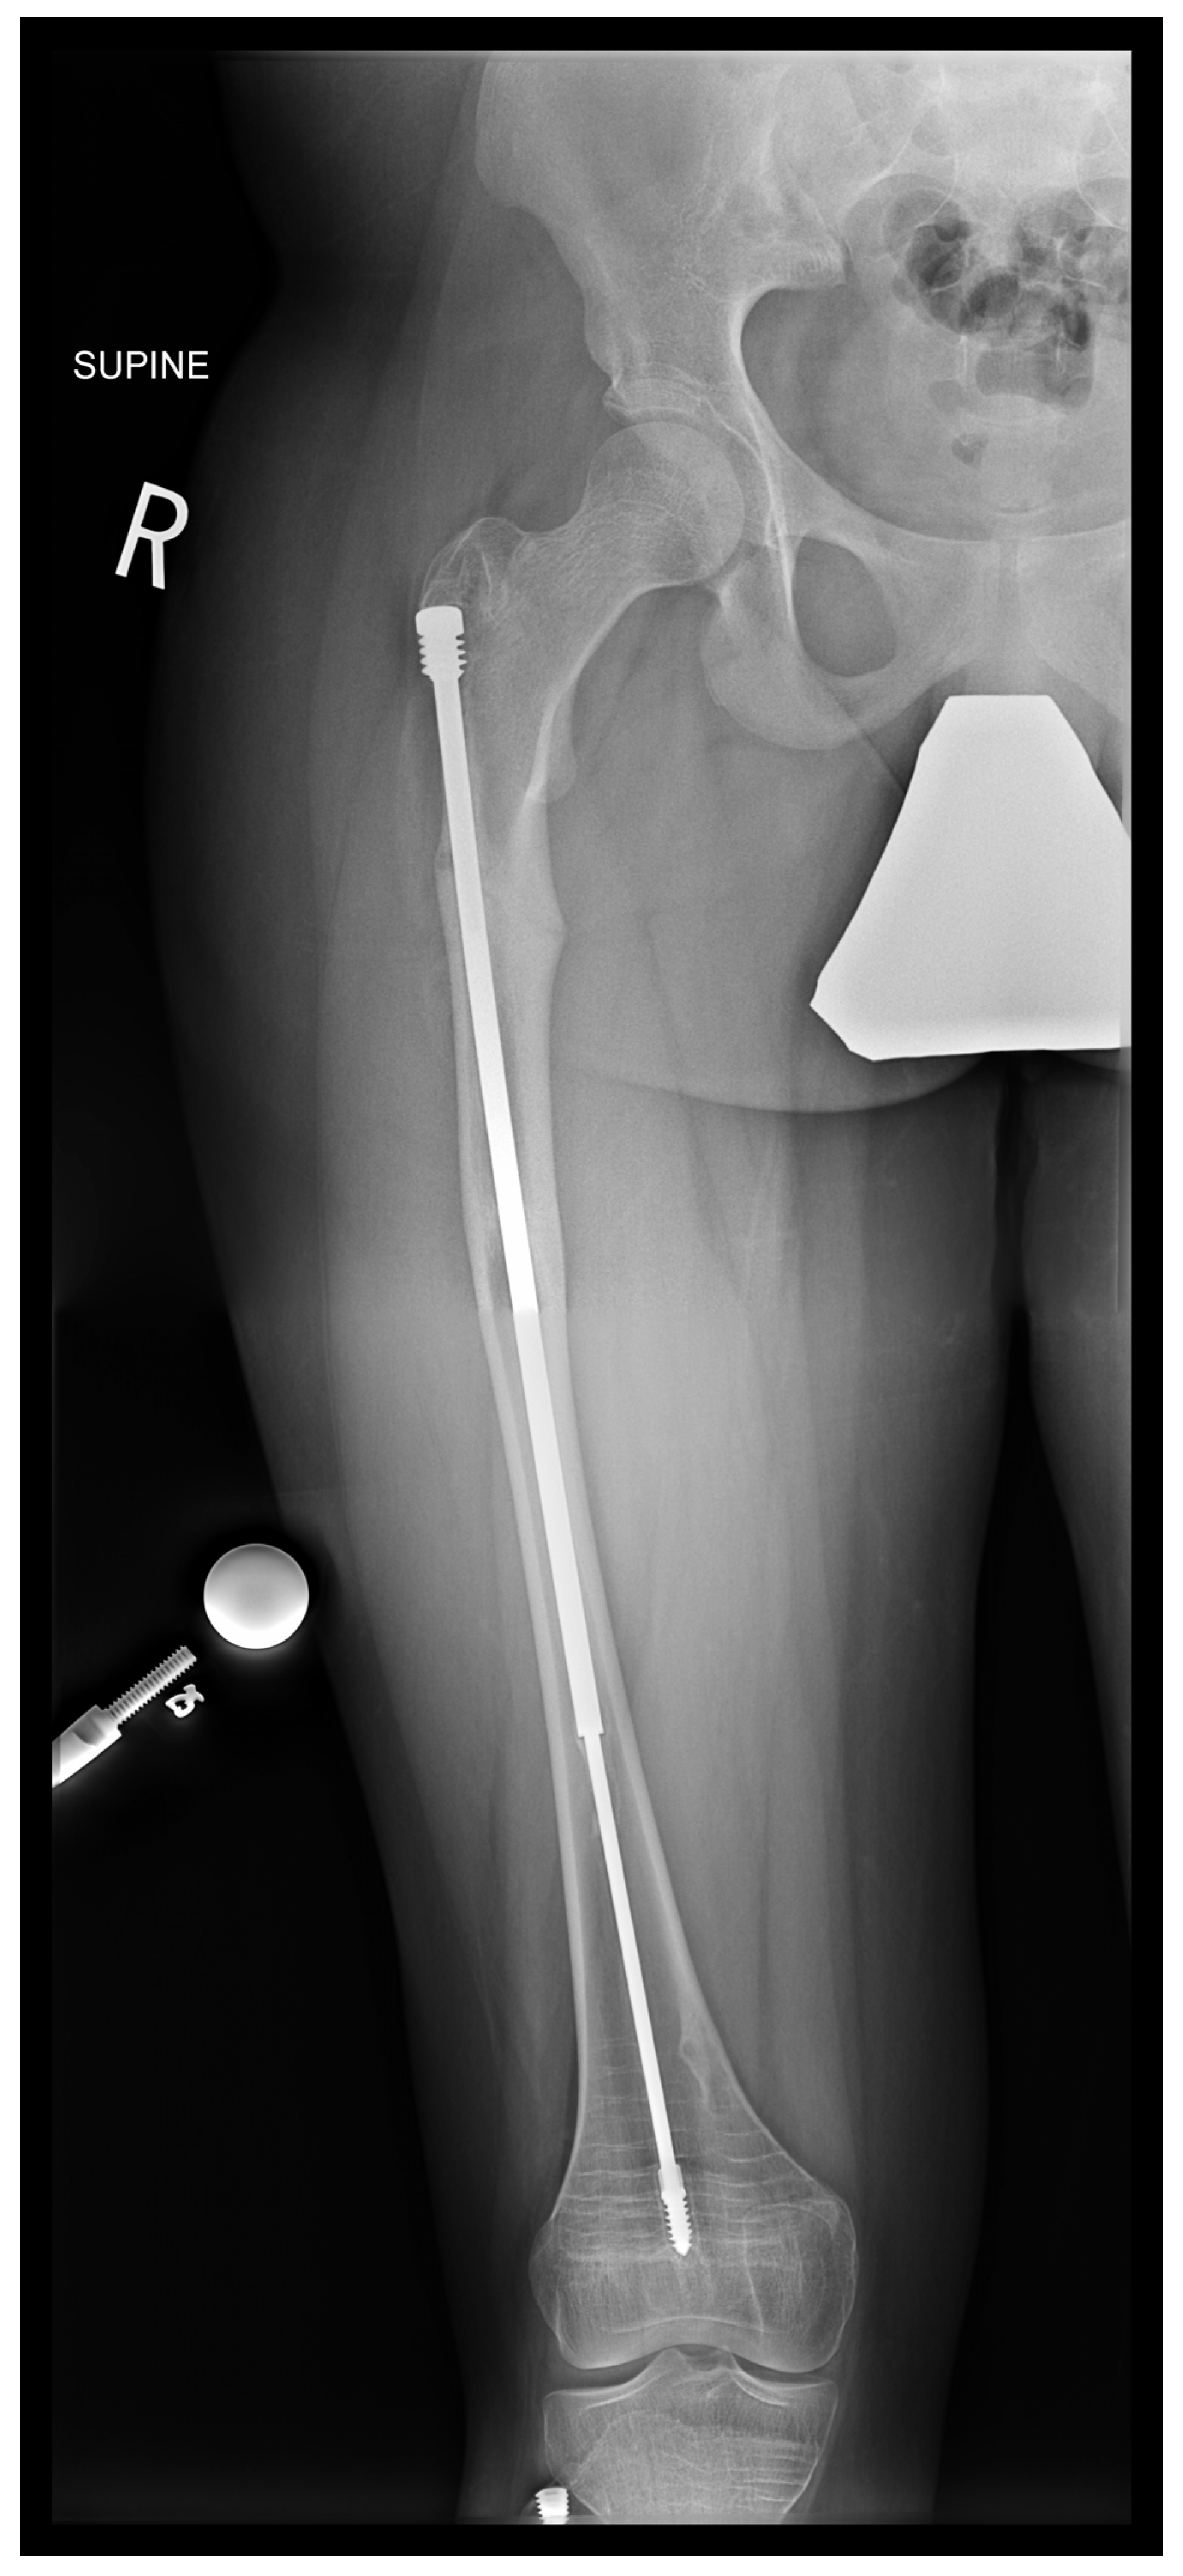

In the third case, a 16-year-old skeletally mature patient with OI was scheduled to undergo revision from FD rod to SLIM nail after presenting with pain due to stress fractures and wild deformity in his proximal right femur (Figure 11). The FD rod was removed, and then, using a piriformis entry point, access to the femur and proximal reaming was performed. There were two CORAs; the first CORA was identified in the subtrochanteric region, and a percutaneous osteotomy technique was performed to realign the bone, and then reaming was continued (Figure 12). The second CORA was identified, and another percutaneous osteotomy was performed, and the bone was cracked with a closed osteoclasis technique, and then reaming was continued in the distal segment (Figure 13). The SLIM nail was then inserted and had an excellent fit. The subtrochanteric region was under high stress, so a 2.7 Smith and Nephew EVOS plate to further stabilize the segment and control the rotation. Two screws were placed above and below (Figure 14). In this case, the indication for the use of the SLIM nail was the need to revise the existing telescoping FD rod in a skeletally mature patient to a solid nail. As the intramedullary canal was too small to accommodate a larger solid nail, a SLIM nail was used instead. The use of a plate as an adjunct to an intramedullary nail is also shown.

Figure 11.

Pre-operative X-ray showing right femur stress fracture.